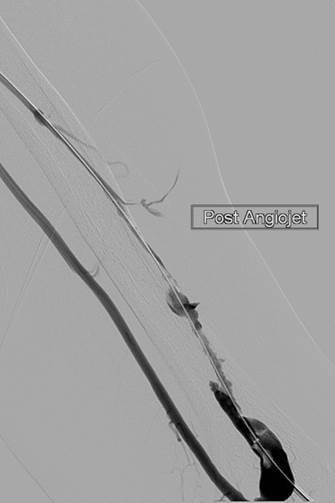

Tras la primera pasada con el catéter DVX de AngioJet (no se usaron trombolíticos).

Tras la segunda pasada con el catéter DVX y la angioplastia con balón de la estenosis subyacente. Sin impedancia para el flujo de avance en la FAV.

Una vez que se establezca el flujo de avance y se trate la estenosis, los trombos residuales deberían resolverse.